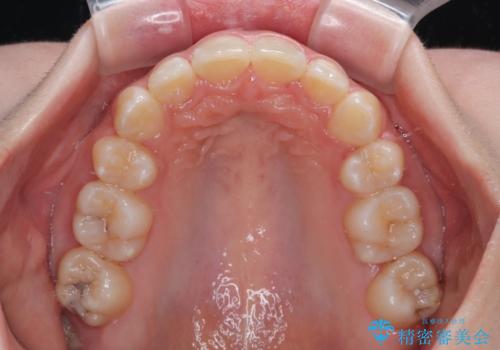

- 上顎前歯の突出感を気にして来院された患者様です。

上下左右第一小臼歯4本を抜歯して、積極的に口元を引っ込めるよう、ワイヤー装置にて矯正治療を行うこととしました。